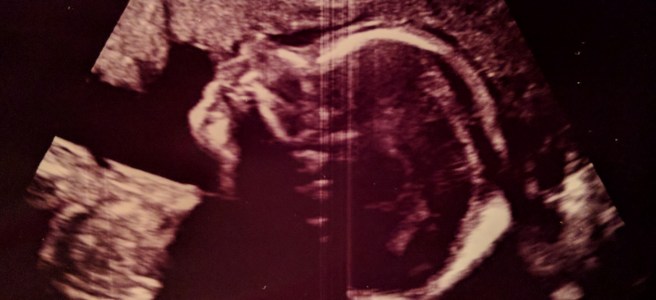

Ich sitze hier und schaue auf meinen schon sehr runden Bauch, sehe die kleinen Beulen, die hier und da kurz zu sehen sind und dann wieder verschwinden. Nie wird es aufhören, mich zu faszinieren, dass da unter dieser dünnen (naja, mitteldünnen 😉 ) Schicht aus Haut, Fett, Muskeln und Faszien ein richtiger kleiner Mensch wohnt und wächst. Mein kleines Mädchen! Weiterlesen